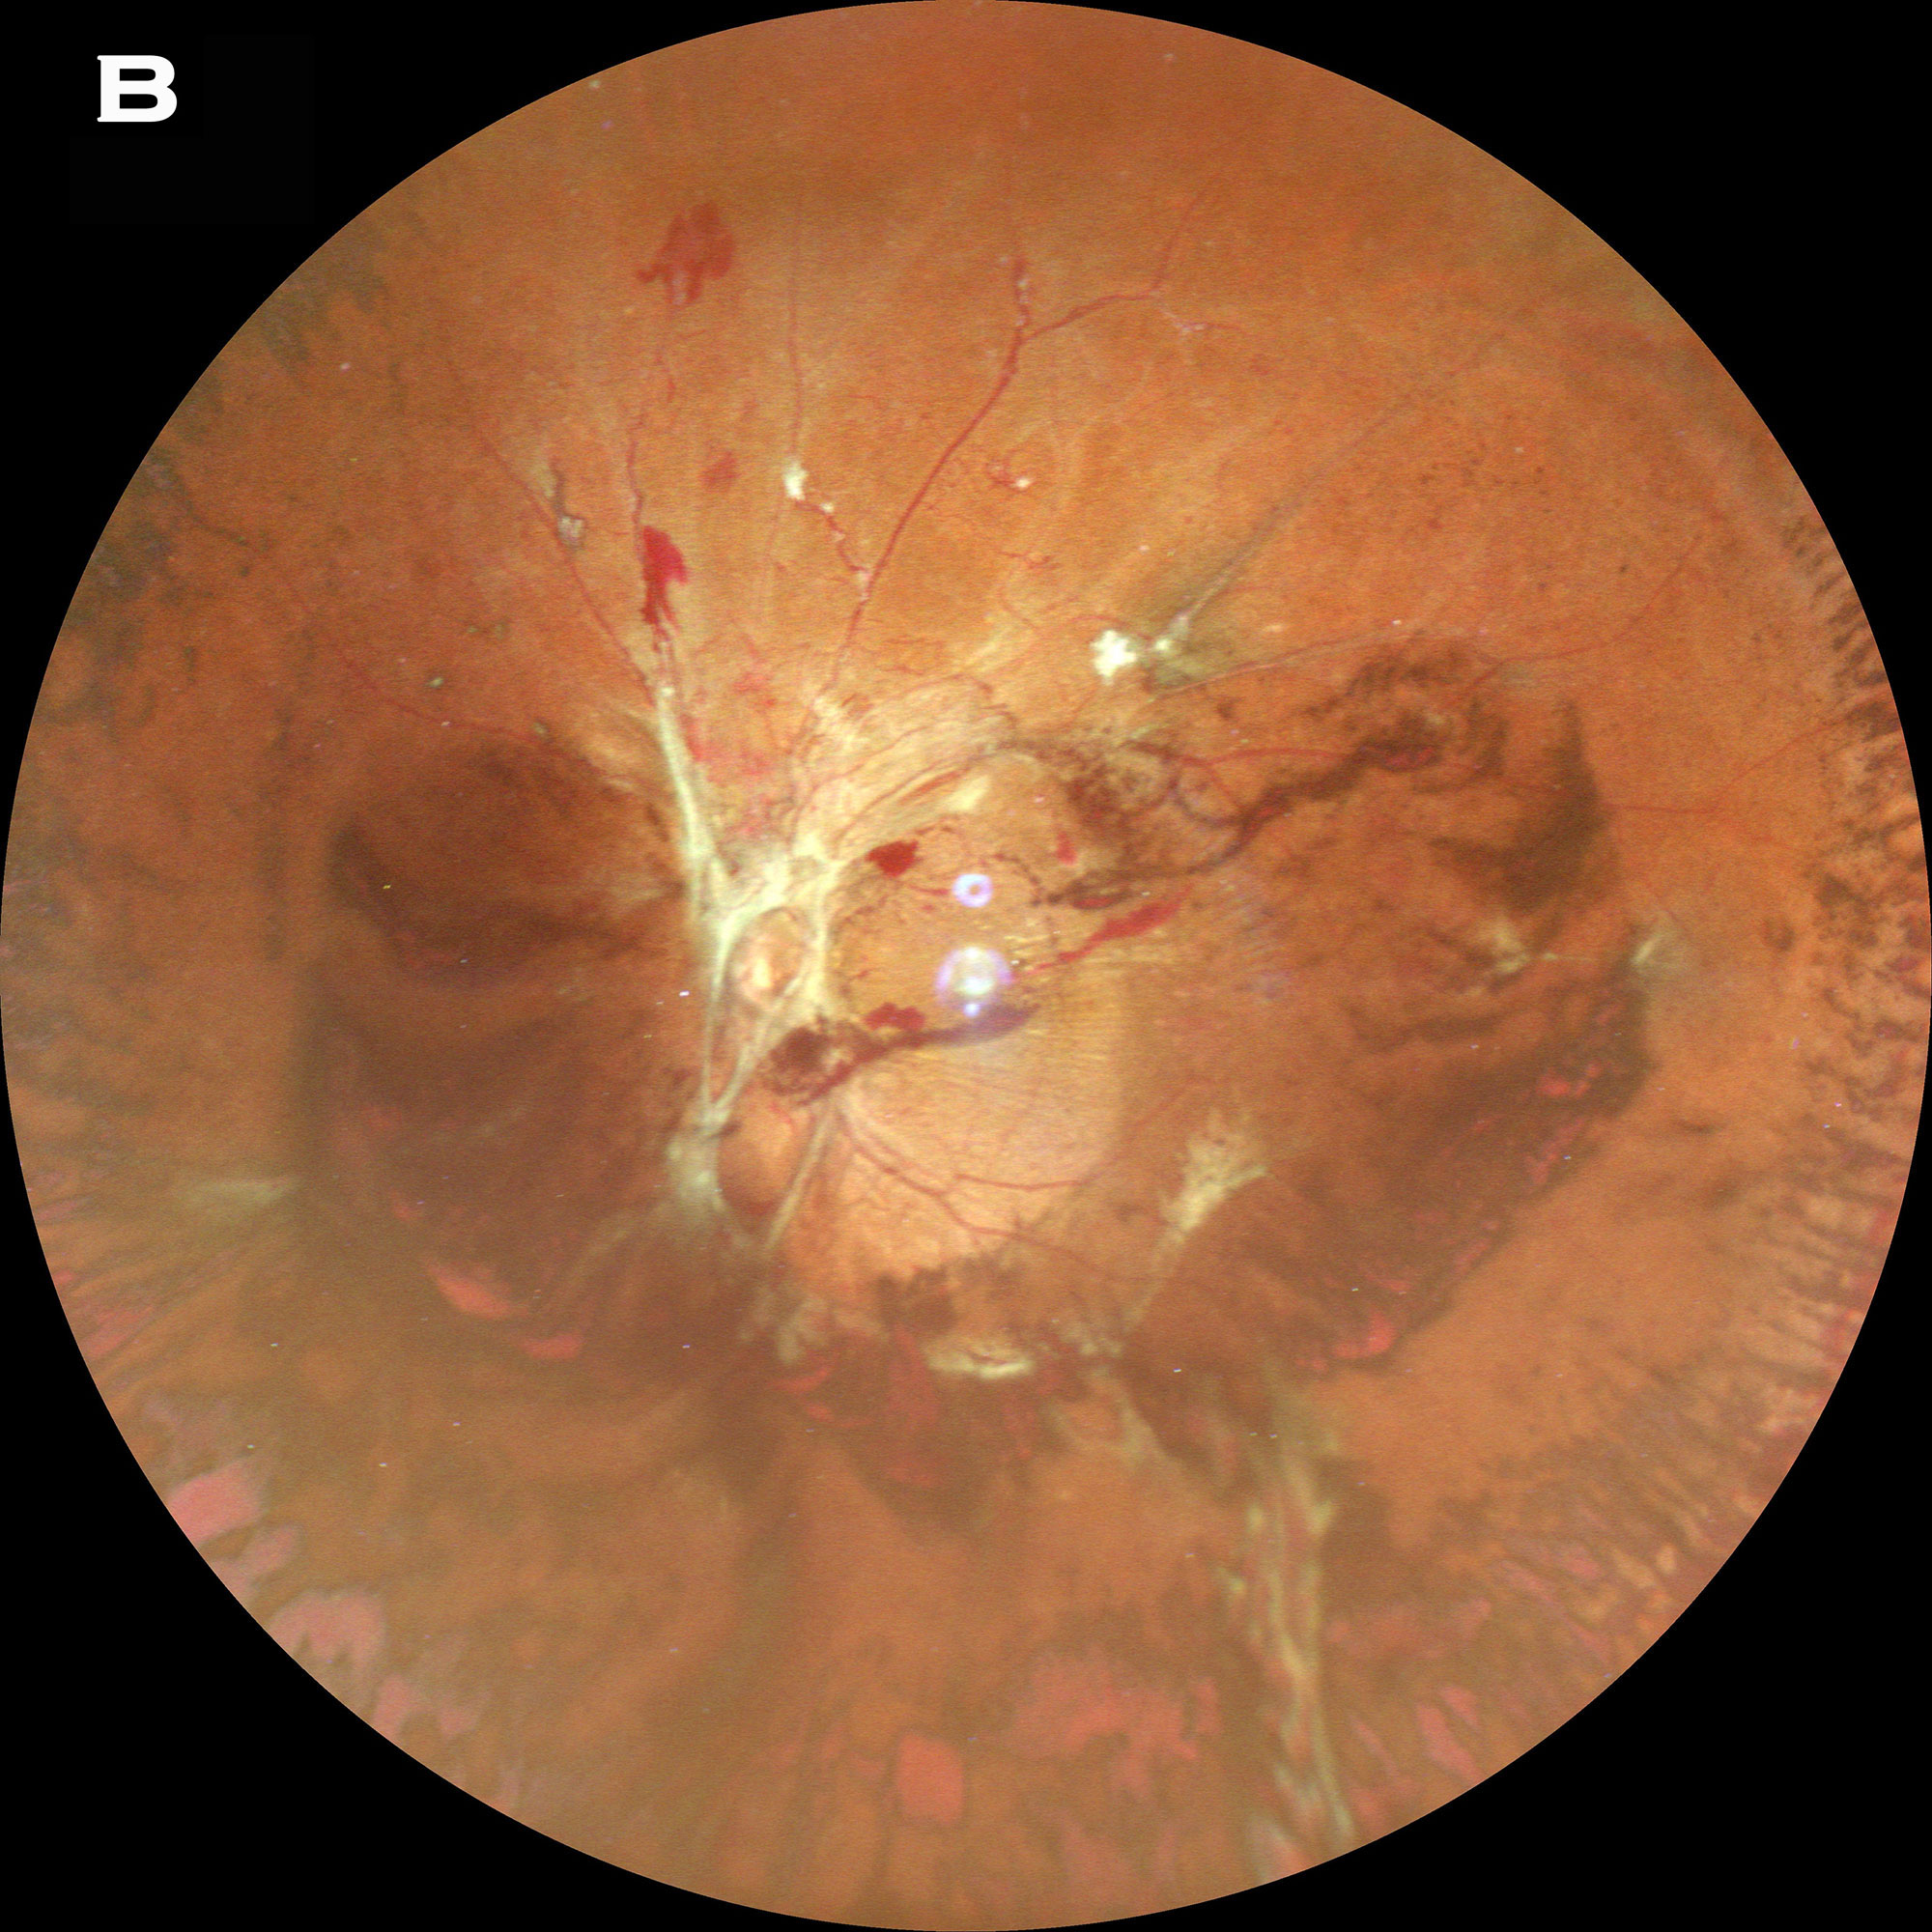

34歲男性糖尿病患者,主訴雙眼視力模糊2個多月。根據他的醫療記錄,右眼初始BCVA為20/100,左眼為20/125。雙眼前節無明顯異常。眼底成像顯示雙側增殖性糖尿病視網膜病變(PDR),視盤區域有增殖的纖維組織,左眼伴隨玻璃體出血(圖1)。此外,OCT顯示視網膜海綿樣腫脹,左右眼中央黃斑厚度分別為339μm和413μm。基于雙眼PDR合并黃斑水腫的診斷,由另一名醫生進行雙眼璃體腔內注射抗血管內皮生長因子藥物(Anti-VEGF)。然而,治療后2周,左眼視力從20/125下降到20/250,發現累及黃斑的牽拉性視網膜脫離(TRD)(見上圖)。因此,他被轉到我們門診接受進一步治療。

圖1. Mirante超廣角眼底彩照可見雙眼PDR,右眼視盤鼻側合并增殖的纖維組織(A)以及左眼視盤和血管弓上方圓環樣的增殖纖維組織和玻璃體出血 (B)。